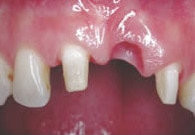

Fehlenden Schneidezahn mit einem Implantat ersetzen

Röntgenbild mit Schraubimplantat

Das Röntgenbild mit dem Implantat und der provisorischen Klebebrücke.